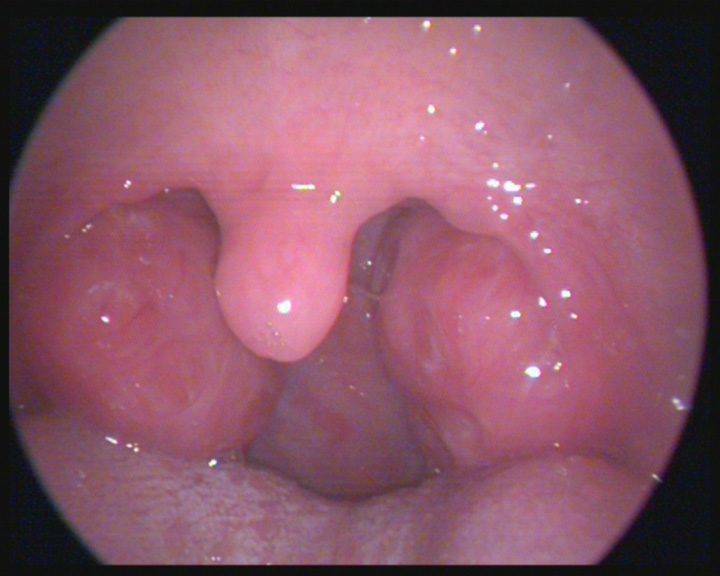

Bu videoda; Bademcik ameliyatı sonrası dikkat edilmesi gerekenler, bademcik ameliyatı sonrası kullanılan ağrı kesiciler konularını izleyebilirsiniz.

Bademcikler Ne Zaman Alınmalı?